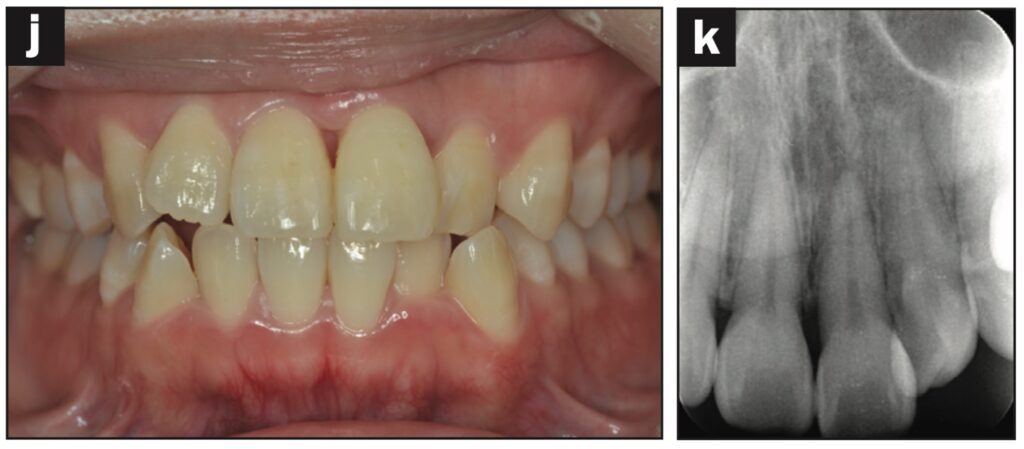

Bệnh nhân nữ 42 tuổi bị ngã khiến răng cửa giữa hàm trên bên trái bị lệch về phía vòm miệng. Đường gãy xương ổ răng ở phía khẩu cái được thấy trên CBCT.

Răng được nắn chỉnh và cố định bằng composite quang trùng hợp rồi lấy dấu. Hai tiếng sau, bệnh nhân quay lại và nhận khay duy trì. Bệnh nhân được hướng dẫn đeo khay duy trì cả ngày trừ khi đánh răng.

Các thử nghiệm tủy được thực hiện sau 7 và 28 ngày. Đánh giá độ lung lay răng, gõ và sờ, thử tủy EPT và chụp X quang được thực hiện sau 28 ngày.

Sau 28 ngày theo dõi, răng hơi lung lay và không đáp ứng với thử tủy EPT. Sau 2 tháng theo dõi, răng không bị đổi màu, không lung lay, âm tính với EPT và hơi nhạy cảm khi gõ. Không có tổn thương quanh chóp trên X quang và không có lỗ dò. Sau 3 tháng theo dõi, răng đã đáp ứng với EPT (9/10) và có cảm giác đau nhẹ khi gõ.

Sau 4 tháng theo dõi, răng đã phản ứng với EPT (9/10) và không còn nhạy cảm với gõ.